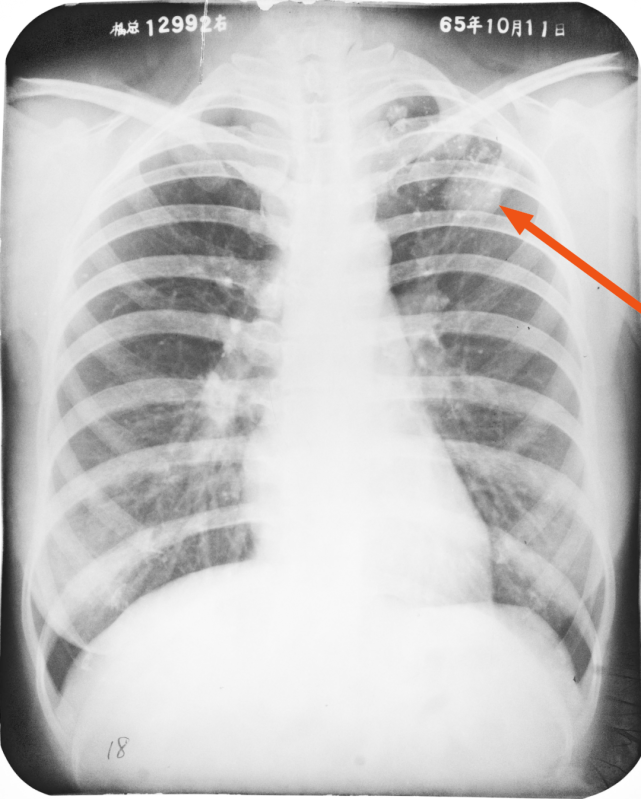

左上肺结核球(箭头所指)

图片

左肺上野斑片状、条索状密度增高影,箭头所指处规整结节影,周围可见多发卫星灶及钙化